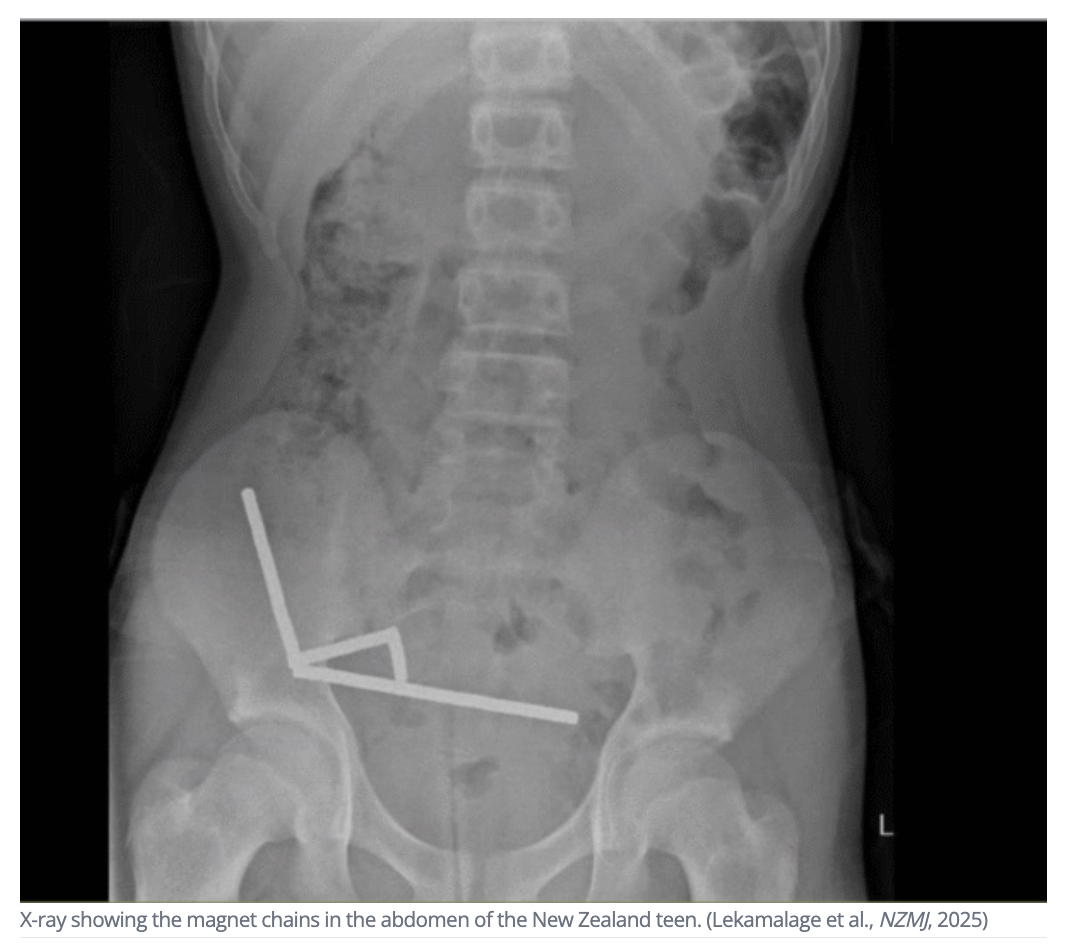

ニュージーランドの病院に、激しい腹痛を訴える13歳の少年が運び込まれた。問診に対し、彼は「1週間ほど前に、磁石を100個くらい飲み込んだかもしれない」と告白。しかし、X線撮影で明らかになったのは、彼の想像を遥かに超える、おびただしい数の磁石だった。その数、実に200個近く。少年の腹の中で、強力な磁石は互いに引き寄せ合い、彼の内臓を静かに破壊していた。

少年の体内にあったのは、「ネオジム磁石」と呼ばれる、通常の鉄の磁石の最大50倍もの磁力を持つ、極めて強力な磁石だった。飲み込まれた200個近くの小さな磁石は、腸の中を移動するうちに、腸壁を隔てて互いに引き寄せ合い、“合体”してしまった。

X線写真には、数珠つなぎになった磁石の鎖が、腸の異なる4箇所で確認された。腸壁は、内外から強力な磁石に挟み撃ちにされ、血流が途絶え、組織が壊死する「圧迫壊死」という深刻な状態に陥っていた。

医師団は、緊急手術で磁石をすべて摘出したが、壊死した腸の一部を切除せざるを得なかった。幸いにも手術は成功し、少年は8日後に退院できたという。